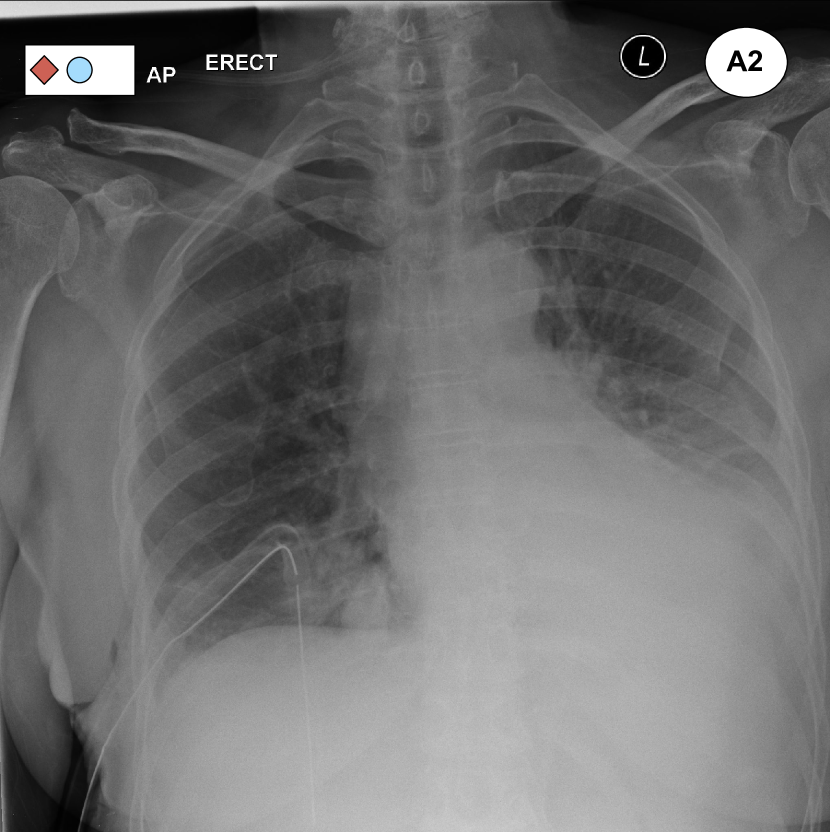

Figure 1: Examples of pairs of images that are placed close to each other in the learned embedding space shown in Fig. 3. A1 was incorrectly reported, but a second reading shows the presence of pleural effusion and a medical device, which justifies its proximity to A2. B1 was labelled as “normal”, but a second reading reveals some degree of cardiomegaly and, as such, the scan is placed close to B2. An extract from the original reports can be found under each image. Fig. 3 contains the legend for the labels.

Figure 3 shows a 222-dimensional representation of the 2,25222522,252 radiographs contained in the Golden Set. This representation was obtained by means of dimensionality reduction using a t𝑡t-distributed Stochastic Neighbor Embedding (t-SNE) [16], which effectively projects the 646464-dimensional embeddings extracted from the best model onto 222 dimensions for visualisation purposes. Remarkably, this projection shows that the normal exams are mostly concentrated in a well-separated cluster; moreover, other clusters of exams sharing similar abnormalities have also been identified.

The chest radiographs marked with a circle can be seen in Figure 1. These are two examples of radiographs that were originally labelled as normal but ended up being placed away from the cloud of normal exams. A second reading of these exams has revealed unreported abnormalities thus confirming that their position within the embedding was justified.

Figure 3: 222-dimensional embedding of all chest radiographs contained in the golden dataset learned through the ML2+ loss and visualised via multi-dimensional scaling. Each exam is represented as a point with different shapes and colors to identify multiple labels. Well-separated cluster of “normal” radiographs (green triangles) and exams featuring an enlarged heart are clearly visible. See Fig. 1 for the circled images.